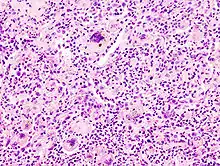

![]() Melanom-Metastase im Lymphknoten. |